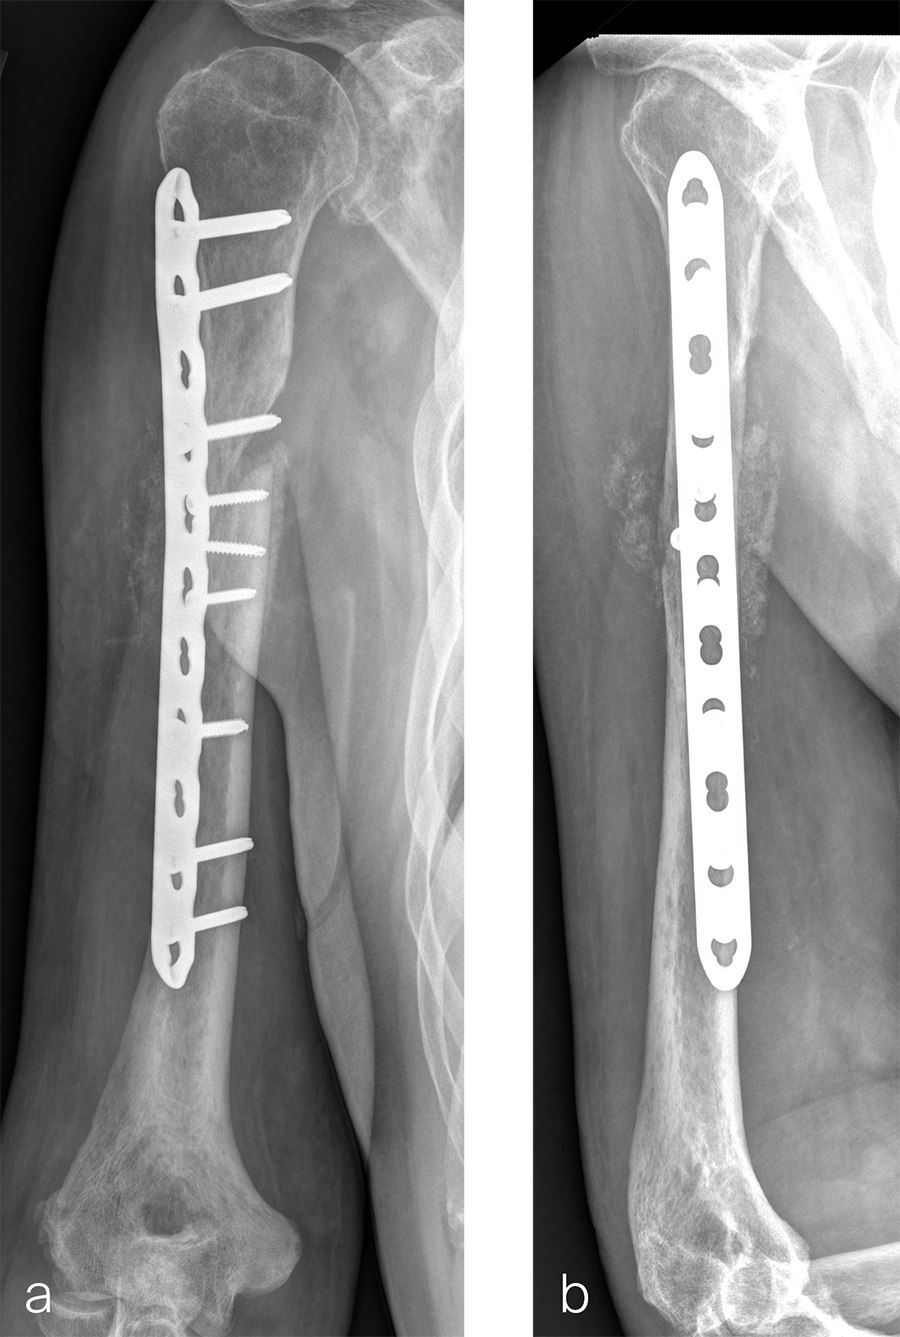

Two months later, the patient had a staged cement spacer removal and hardware removal followed by a new spacer placement (Fig 4). When microbiological cultures were negative for 5 days he was taken to the OR for definitive fixation and bone grafting. RIA bone graft from the ipsilateral femur was taken, a new anterior lateral plate was placed with an adjunct IM nail (and angle stable screws) as the distal plafond was now one articular block (Fig 5).

The patient has been followed up monthly for more than 5 months and has shown continued consolidation of the bone defect (Fig 6). Furthermore, he is weight bearing as tolerated without significant pain. The leg lengths are equal and the range of motion at the ankle is 10/25 dorsiflexion/plantarflexion. He has mild pain over the ankle joint but no pain at the fracture site.